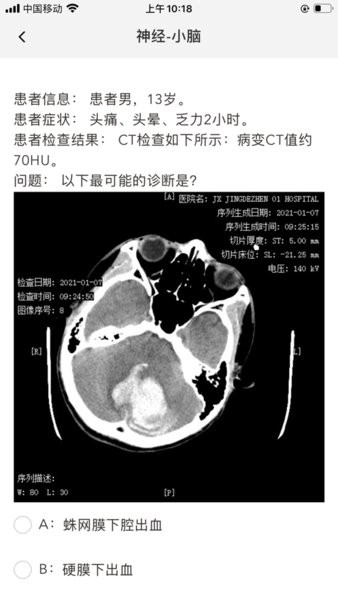

星火影像住培是专为影像从业者量身打造的学习平台,汇聚海量习题资源,涵盖专科教学、读片技巧、报告书写等多个模块,助你全方位提升专业技能。通过亚专科教学、问题导向学习法、评价考核、报告书写和阅片技能培训等五环节,打造系统化学习路径,无论新手或资深专家,都能找到适合自己的进阶之路。充分利用碎片时间,随时随地,让学习成为一种生活方式。

星火影像住培基于SPARK软件体系,以亚专科教学为基础,辅以问题导向学习法,激发主动探究精神。我们的评价考核机制确保每个学员都能得到个性化评估,报告书写功能则强化了书面表达能力的训练。同时,强大的阅片技能培训模块,让你的读片技能更上一层楼。无论是手机还是电脑,随时随地,轻松接入,让学习无界限。

1、多元化学习模式:提供练习、快刷、测试、背题等多种做题模式,满足不同学员需求,助力快速掌握知识点。

2、权威解析与互动:优质详细的考点解析,结合名师互动的免费公开课,让学习更深入,体验更丰富。